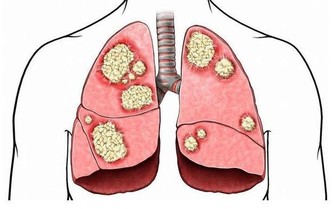

●「足太陽膀胱經」是人體免疫力 守護神!如何避免風邪入侵有法寶 ,節目中大公開。